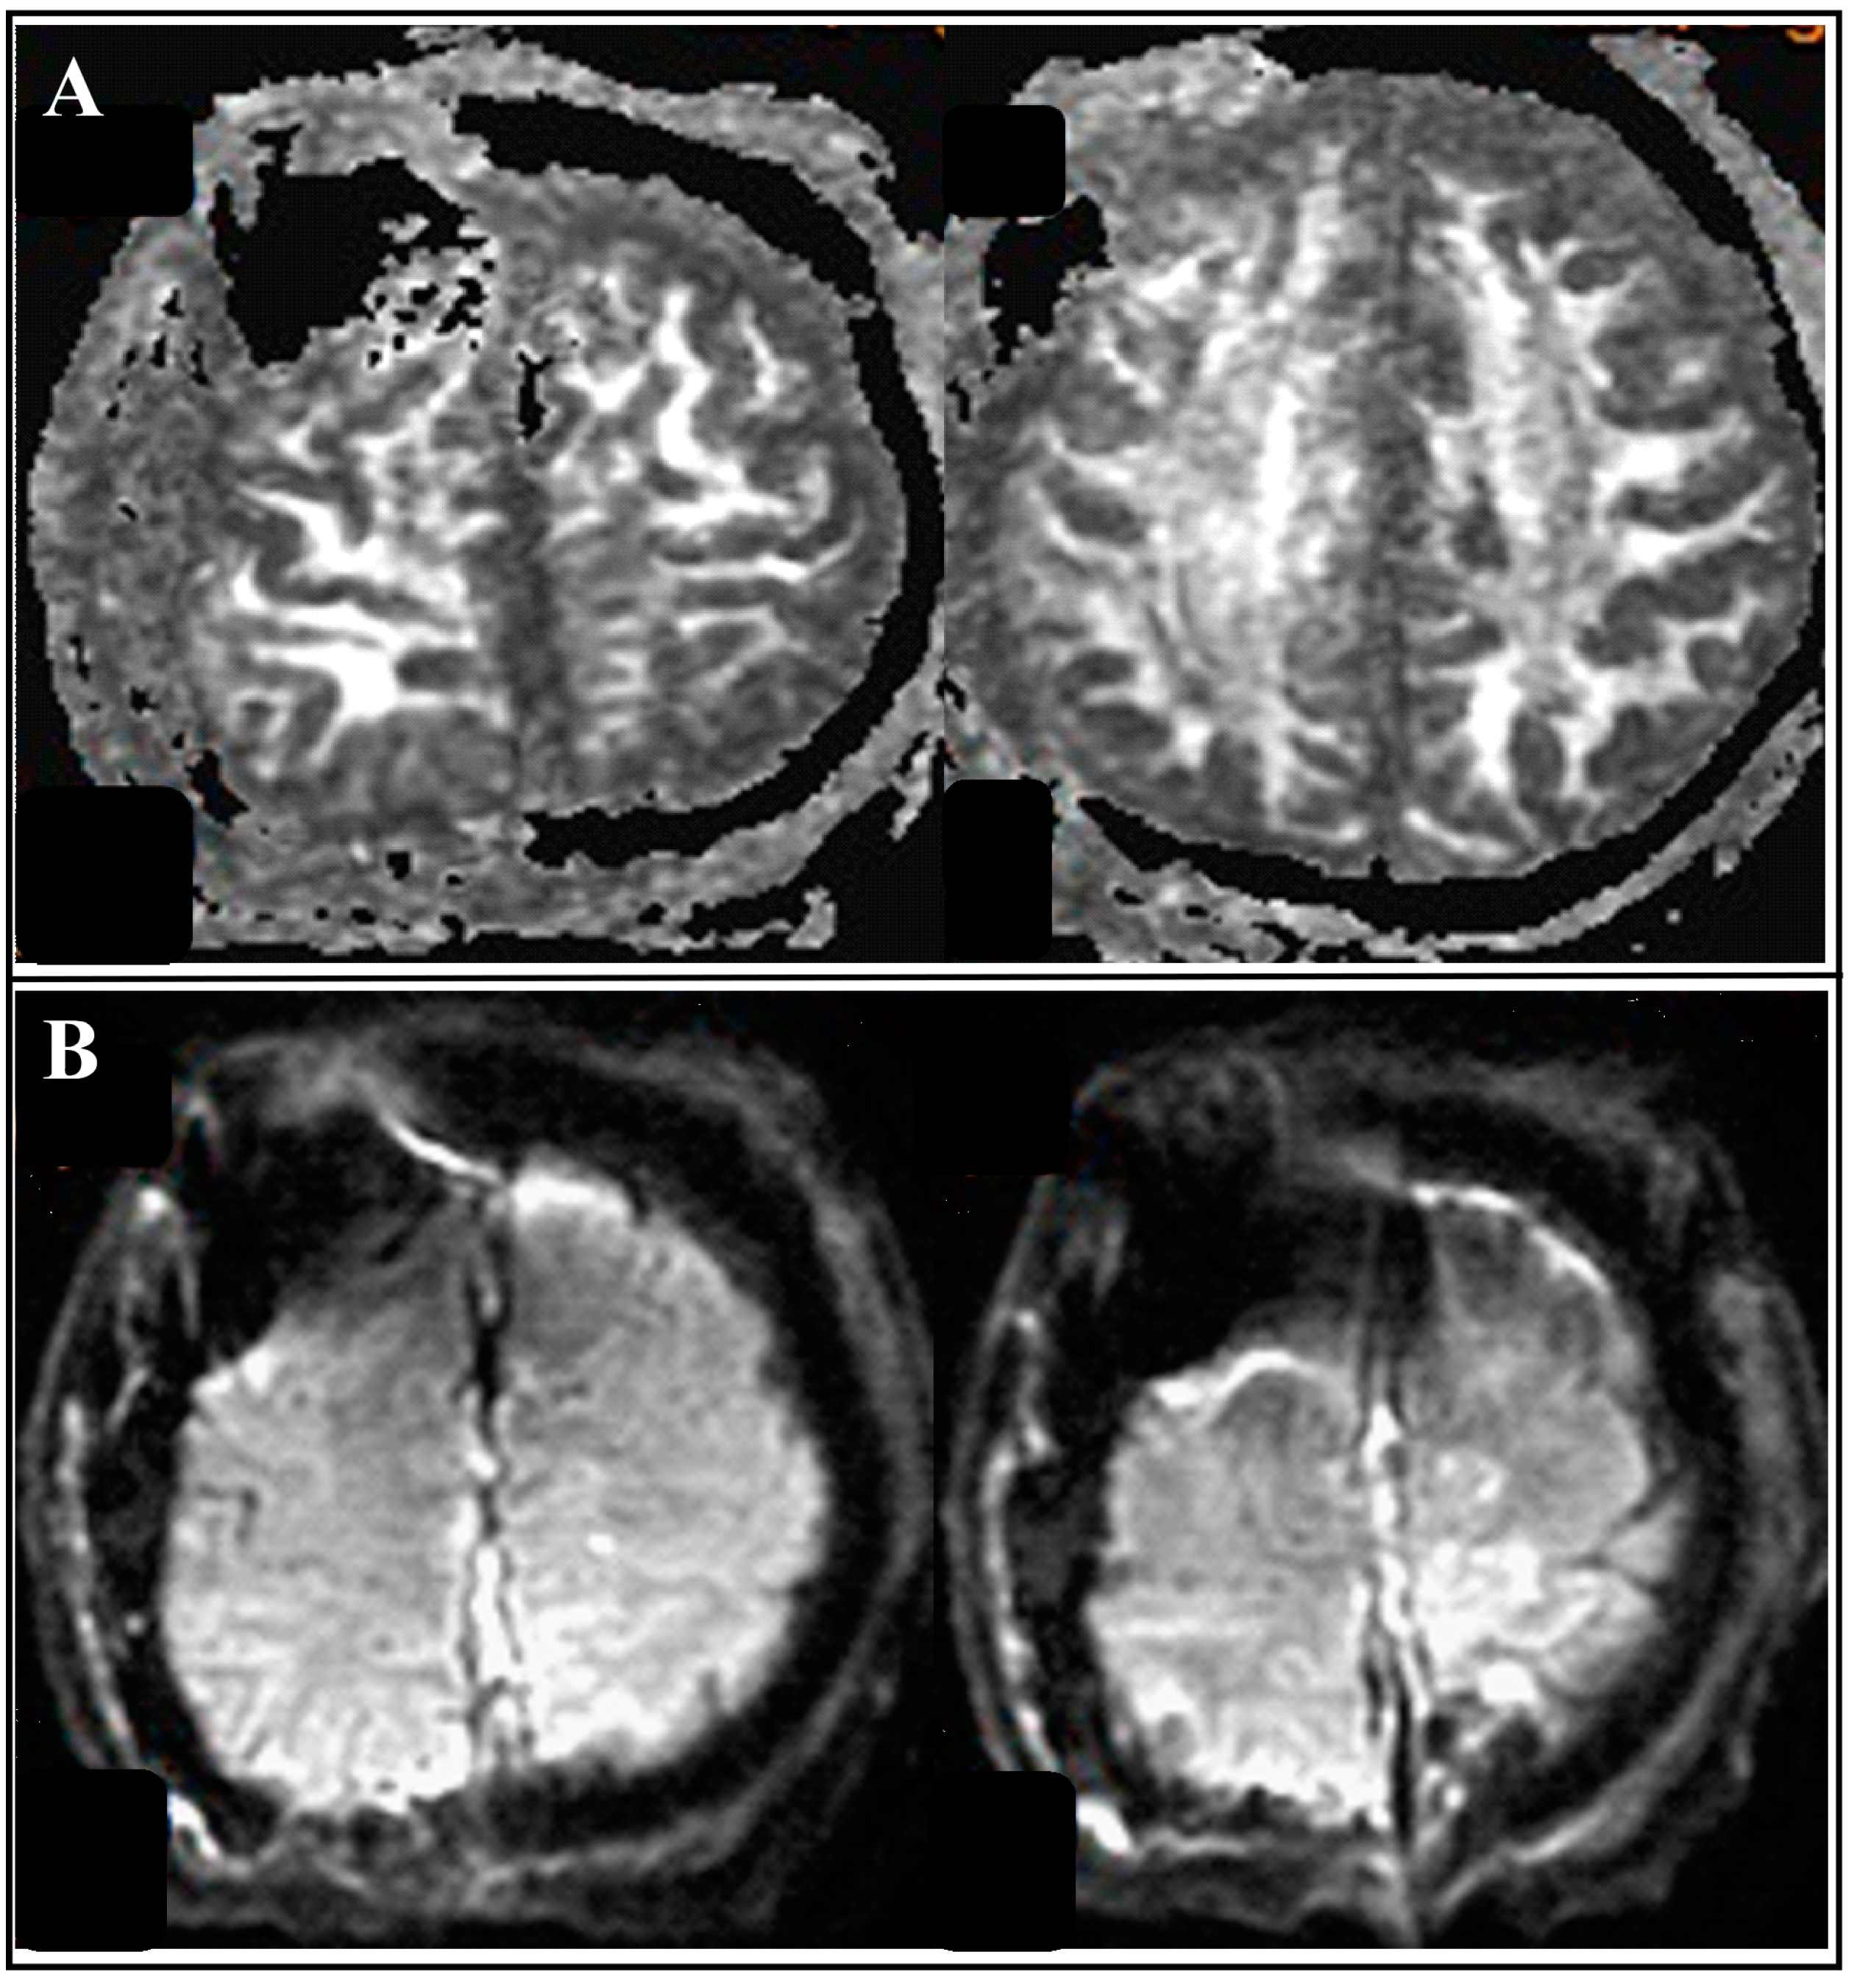

2.1. Our Case Description

| Tsai et al., 2021 | 55/M | Seizure, loss of consciousness | 91 | bilateral | occluded | II | I | 2/5 left arm and left leg 0/5 right leg | Preserved | Aphasia | Aphasia recovery within 7 days; muscle power recovery within 7 weeks |